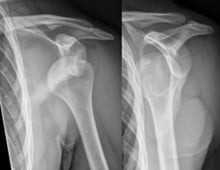

A 21-year-old male walks into the emergency department complaining of right shoulder pain after a fall to the ground during a pickup basketball game. He is clutching his right arm in abduction and external rotation. You perform a focused physical exam, noticing a flattened contour of the shoulder. X-ray confirms your suspicion of anterior shoulder (glenohumeral) dislocation. You discuss your findings with the patient and explain the need for a closed reduction. He then grimaces and asks, “Is it going to hurt?”

"Dislocated shoulder X-ray 10” by Hellerhoff

Shoulder dislocations make up about half of all major joint dislocations encountered in the emergency department.1 Due to pain and the risk for neurovascular compromise, it is important that the joint be reduced promptly. There are several challenges to a successful reduction: spasm of the shoulder girdle muscles due to abnormal stretching,2,3 bony friction between the humeral head and glenoid, and patient discomfort. All reductions must use a combination of analgesia or technique to overcome these forces acting on the dislocated humerus. There have been >50 reduction techniques described in the literature, with no clear consensus of the superiority of one technique over another. Regardless of technique used, given the psychological and physical trauma associated with a closed reduction, it is essential that adequate pain control be a top priority. In this article, we will discuss the advantages and disadvantages of three different pain control approaches: procedural sedation, intra-articular injection, and interscalene nerve block.